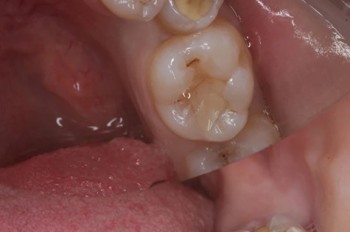

Кхалил Абаноуб Адли Абдуллах: портфолио (4)